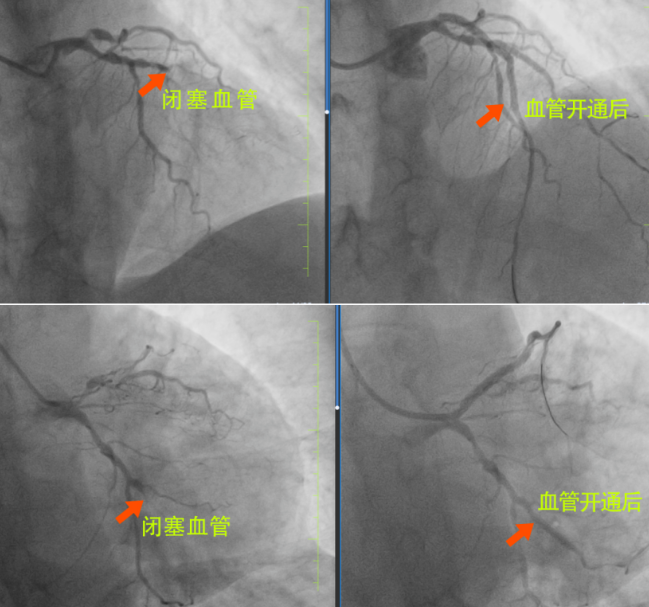

很快,長春國文醫(yī)院心內(nèi)科為患者安排了手術(shù),為患者進(jìn)行手術(shù)的是長春國文醫(yī)院副院長、心血管中心主任隋立有。隋院長在心血管領(lǐng)域造詣深厚,擁有豐富的臨床經(jīng)驗(yàn)。隋院長始終專注于心血管疾病的研究與治療,對(duì)各類復(fù)雜心血管病例有著獨(dú)到的見解和精準(zhǔn)的判斷。隋院長在了解患者的病情后,迅速制定了治療方案。患者3根血管完全閉塞,情況十分危急。但隋院長憑借著精湛的醫(yī)術(shù)和豐富的經(jīng)驗(yàn),巧妙地開通了2根血管,整個(gè)手術(shù)過程僅僅用了不到半小時(shí),就成功完成了3枚支架的植入。這一高效且精準(zhǔn)的手術(shù),讓患者和家屬驚嘆不已,也讓他們真切地感受到了國文醫(yī)院心內(nèi)科雄厚的師資力量和成熟的技術(shù)實(shí)力。